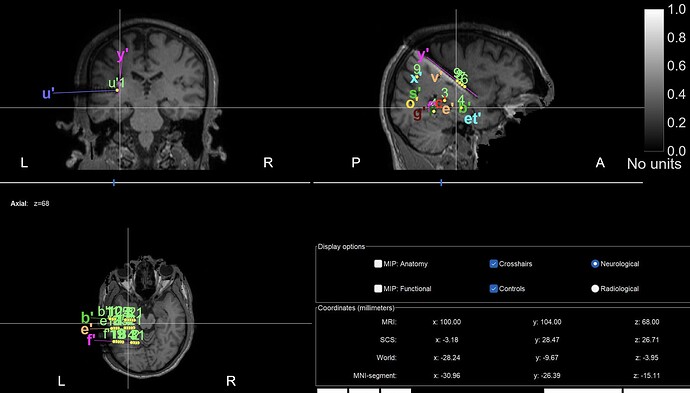

I'm currently doing this Tutorial with Matlab R2025a :

I am near the end of the tutorial where we use the Epileptogenicity maps > Surface but it doesn't work. Here's the error message :